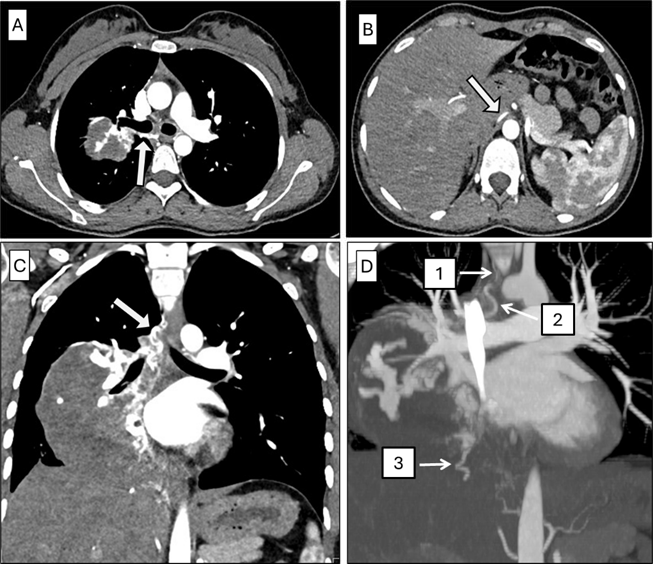

Incidental Finding of a Retroaortic Left Renal Vein with Pelvic Venous Congestion Consistent with Posterior Nutcracker Syndrome: A Case Report

Antonia Berz, Théo Sartoretti, Rami Hajri, Guillaume Fahrni